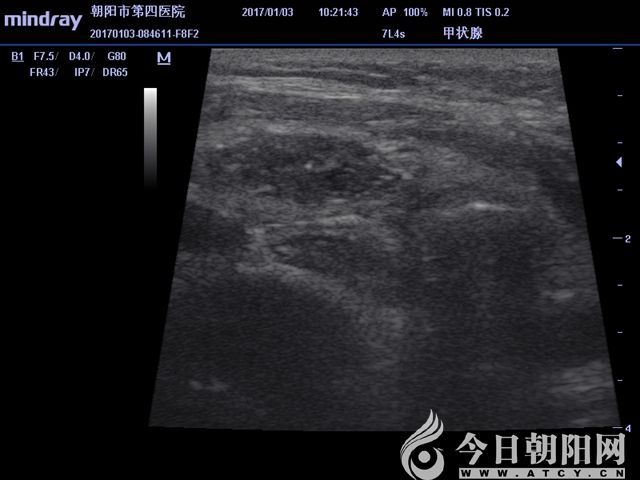

抽液后超聲顯示實(shí)性結(jié)節(jié)

抽液后超聲顯示實(shí)性結(jié)節(jié)范圍

微波消融針穿刺至實(shí)性病變處,根據(jù)超聲引導(dǎo),調(diào)整消融針,連續(xù)消融,至病變區(qū)域全部達(dá)到熱容效應(yīng)?;颊咴谑中g(shù)中始終保持清醒,無(wú)明顯疼痛等不適感,偶有咽喉部輕度的腫脹感。術(shù)后4小時(shí),患者離床活動(dòng),飲水無(wú)嗆咳,聲音無(wú)嘶啞。術(shù)后第3天,患者恢復(fù)良好,現(xiàn)已出院。